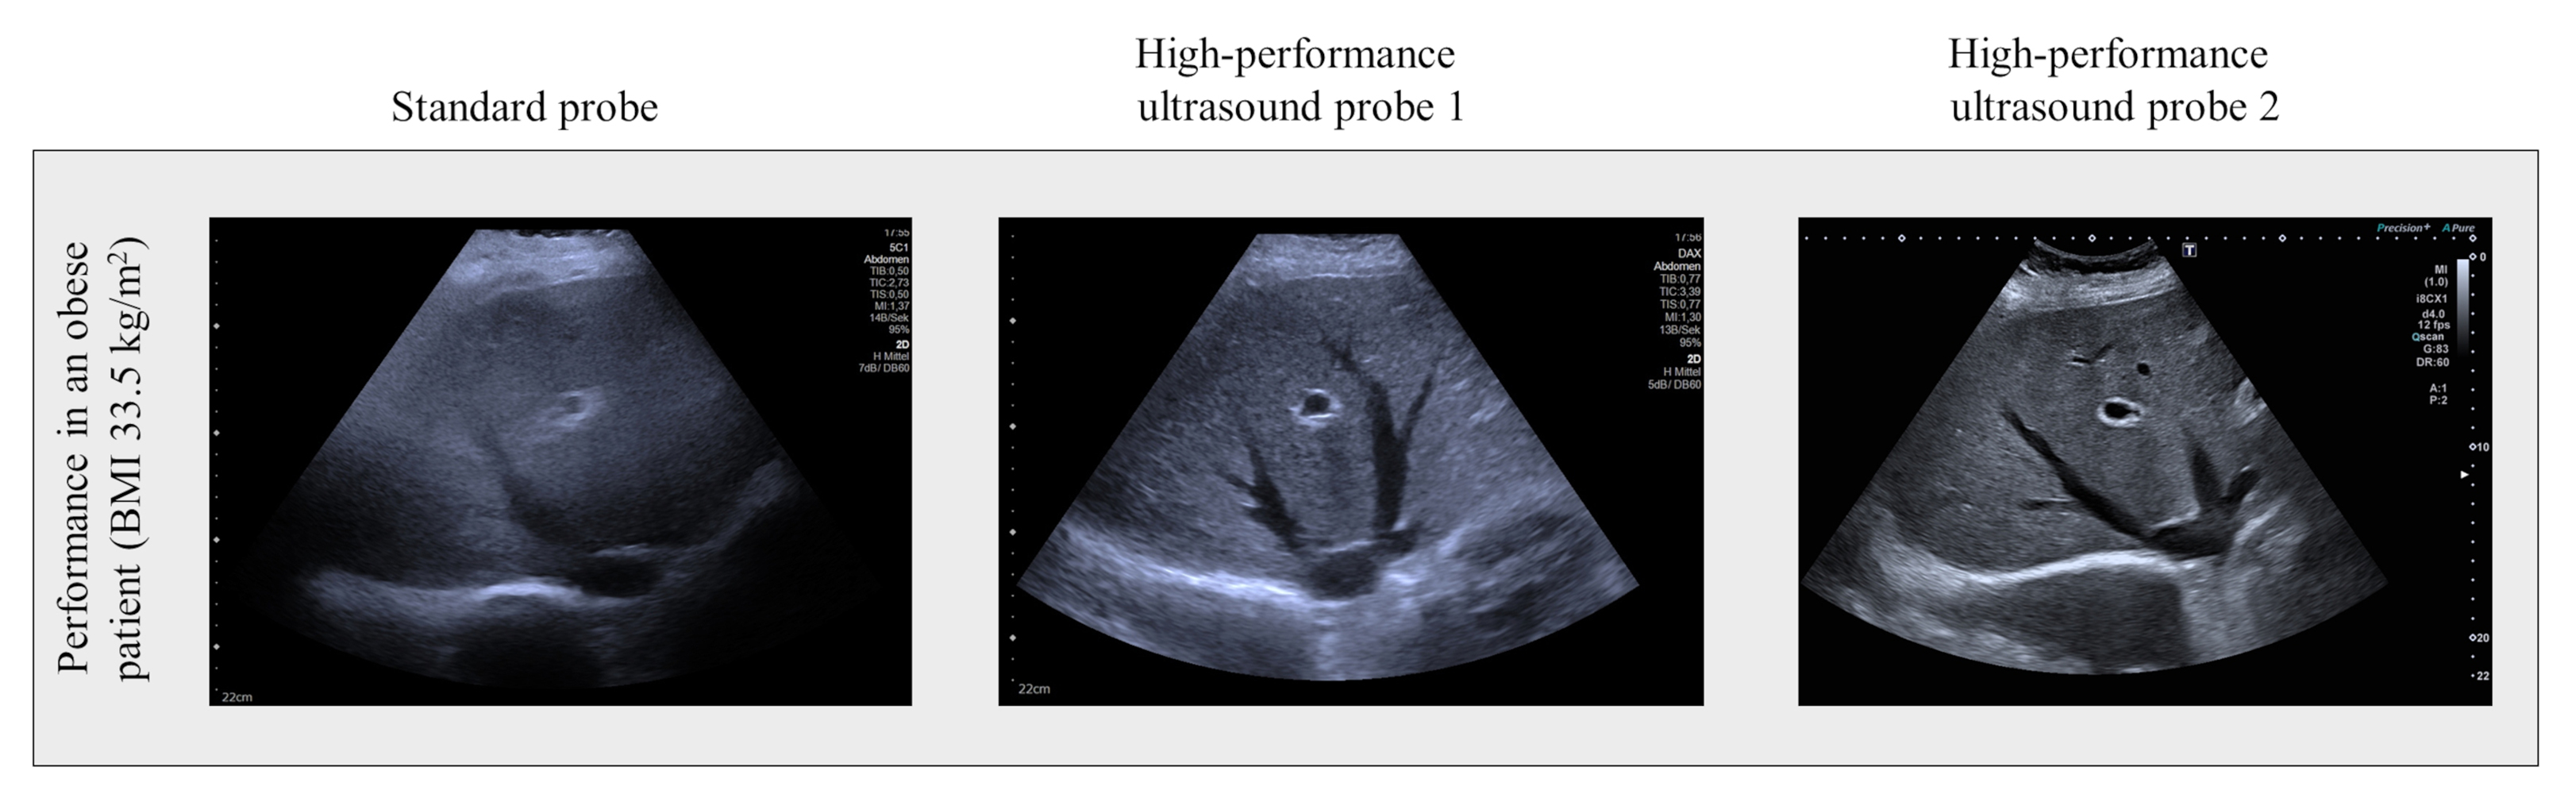

In einer aktuellen klinischen Studie der Universitätsmedizin Leipzig fanden Forschende heraus, dass die Qualität des Ultraschalls bei Leber- und Nierenuntersuchungen bei Patient:innen mit Adipositas deutlich beeinträchtigt ist. „Die Ergebnisse zeigten: Je höher der Body-Mass-Index der Teilnehmenden war, desto schlechter war auch die Bildqualität des Ultraschalls. Außerdem wurde deutlich: Moderne Ultraschallsonden mit der sogenannten Matrixtechnologie verbessern die Qualität der Ultraschallabbildung“, erklärt Prof. Dr. Thomas Karlas, Studienleiter und korrespondierender Autor der aktuellen Publikation. Die Matrixsonden besitzen eine verbesserte Sende- und Empfangstechnologie und erreichen dadurch eine höhere Eindringtiefe in das Gewebe. Somit kann eine bessere diagnostische Genauigkeit bei Risikopatient:innen erreicht werden. Bislang gab es noch keine ausreichende wissenschaftliche Bestätigung der Leistungsfähigkeit der Matrixsonden bei Personen mit Übergewicht.

Die aktuellen Daten zeigen, dass die relativ teuren Spezialsonden für Ultraschallgeräte einen relevanten Mehrwert bieten können. Bei den 40 Teilnehmenden der Studie wurde eine hoch standardisierte Ultraschalluntersuchung des Bauchraums mit drei verschiedenen Sonden, Standardsonde versus zwei Hochleistungssonden, durchgeführt. Untersucht wurden die Leber und die rechte Niere bei Menschen mit verschiedenen Graden des Übergewichts. Die Qualität der Ultraschalluntersuchung wurde anhand eines Punktescores bewertet.

„Insbesondere an Zentren, die auf die Versorgung von Patienten mit Adipositas spezialisiert sind, etwa im Bereich der Diabetologie, der Ernährungsmedizin oder der Adipositas-Chirurgie, sollten für die Untersuchung des Bauchraums Ultraschallgeräte mit Matrixsonden vorgehalten werden“, empfiehlt Prof. Karlas. Der Oberarzt und Leiter der Interdisziplinären zentralen Ultraschalleinheit an der Klinik und Poliklinik für Onkologie, Gastroenterologie, Hepatologie und Pneumologie des Universitätsklinikums Leipzig, weist gleichzeitig auf folgendes Problem hin: „Auch wenn Matrixsonden die Ultraschallqualität bei Adipositas verbessern, wird häufig nicht die Qualität erreicht, die bei schlanken Vergleichspersonen ermittelt wurde. Übergewicht bleibt also eine Herausforderung – sowohl als Ursache von Folgeerkrankungen, zum Beispiel metabolische Lebererkrankungen – aber auch als Limitation verbreiteter diagnostischer Methoden.“ In einem Folgeprojekt soll untersucht werden, ob spezialisierte Ultraschall-Anwendungen, wie die Bestimmung des Leberfettgehalts und der Lebersteifigkeit, mit den Hochleistungssonden besser als mit üblichen Methoden funktioniert.